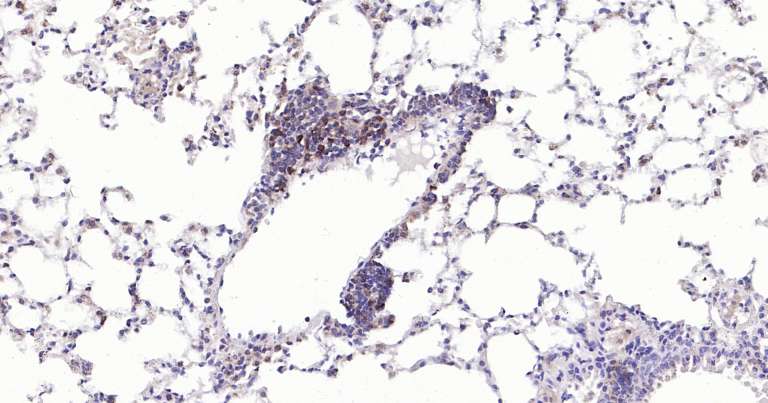

Immunohistochemical analysis of paraffin embedded mouse lung tissue slide using IHC0268 (Caspase-3 IHC Kit).

Immunohistochemical analysis of paraffin embedded rat lung tissue slide using IHC0268 (Caspase-3 IHC Kit).